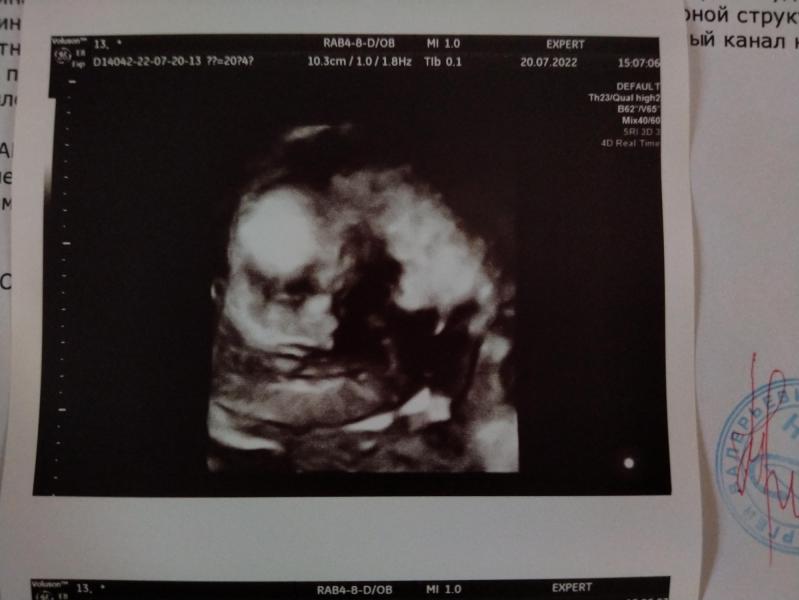

✨✨Я СЧАСТЛИВА! РЕБЁНОК ПОЛНОСТЬЮ ЗДОРОВЫЙ✨✨

и... у нас будет... ❤️ДЕВОЧКА❤️